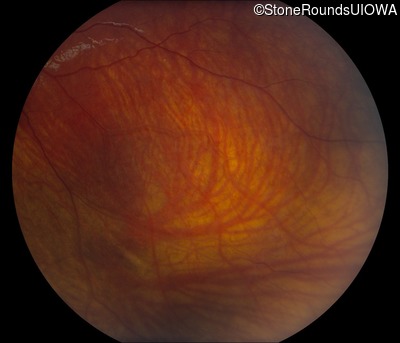

Fundus Photography - Right - 20/63 -2

Exemplar